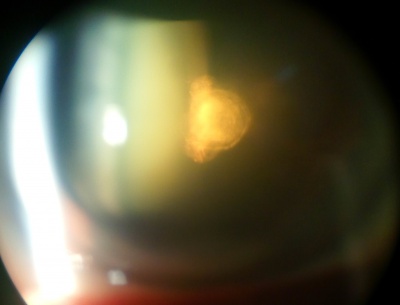

Posterior Polar Cataract

Etiology

Posterior polar cataracts are characterized by well-demarcated white opacities in the center of the posterior capsule. These opacities often project forward as cylinders penetrating into the posterior lens cortex. Posterior polar cataracts are typically congenital with autosomal dominant inheritance.

Symptoms

Most posterior polar cataracts are asymptomatic or minimally symptomatic. However, over time, posterior subcapsular opacities may form around the posterior polar opacity. As the cataract progresses, vision may be severely affected.

Posterior polar cataracts pose a unique challenge for cataract surgery. The rate of posterior capsular rupture is significantly higher in these cases. The posterior capsule is weakened around the posterior polar opacity, and in some cases, there may even be a defect in the capsule.